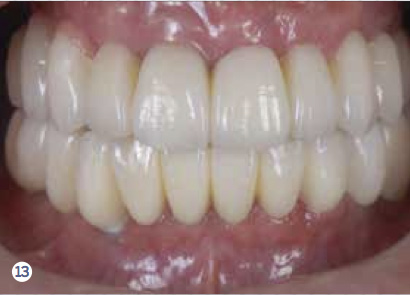

Fig 12 After all the teeth and some implants were extracted, a segmented, screw-retained, implant-supported reconstruction was fabricated and delivered.

Figure 12

Fig 13. After all the teeth and some implants were extracted, a segmented, screw-retained, implant-supported reconstruction was fabricated and delivered.

Figure 13

After evaluating the contingency, priority, and risk, a clinician can determine the prognosis. Because every patient presents with different risks, priorities, and contingency factors, a standard treatment plan will not work for every patient. Therefore, a customized treatment plan is necessary to develop a plan based on the patient’s CPR. For example, utilizing the CPR protocol, a segmented reconstruction can be planned for a patient—if appropriate—that consists of an implant-supported screw-retained restoration (Figure 10 through Figure 15). By combining these three assessment tools, clinicians are able to create better solutions and treatment plans for their patients.